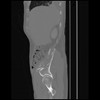

7 CUERPO,CE,Sagittal,3.000,CUERPO,Sagittal,